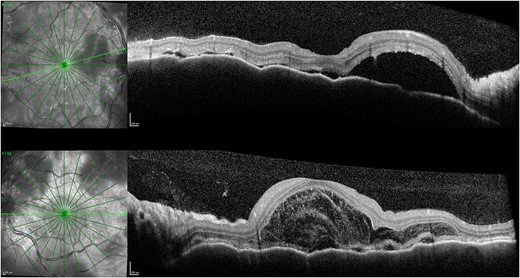

One week after initial review, the patient presented with eye casualty with deteriorated vision of 6/9 in the right eye and count fingers in the left eye. Intraocular pressure was within normal limits in both eyes. Anterior segment examination showed mild anterior uveitis with mild conjunctival injection, 1+ cells in the right eye, 2+ cells in the left eye, and 0.5+ cells in the anterior vitreous of both eyes. No keratic precipitants or posterior synechiae were present in either eye. Fundoscopy revealed bilateral hyperemic discs and 360° choroidal detachments with serous retinal detachment involving the maculae (Fig. 1). There was no evidence of vitritis or retinitis. OCT illustrated detachments of the neurosensory retina and bacillary layers (Fig. 2). Fundus fluorescein angiogram (FFA) demonstrated bilateral disk hyperfluorecence, macular hyperfluorescent pinpoints, and no evidence of retinal vasculitis or ischemia (Fig. 3).

OCT 1 week after initial presentation illustrating neurosensory retinal and bacillary layer detachments, retinal pigment epithelium folds, and darkened choroid pathognomonic for VKH.